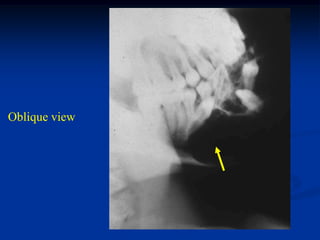

Case #1104.1                Chordoma L-1

49 year male with back

pain for 6 mos and recent

paraparesis

Axial CT L-1 level

Axial T-1         T-2

Gad

Sag T-1   T-2